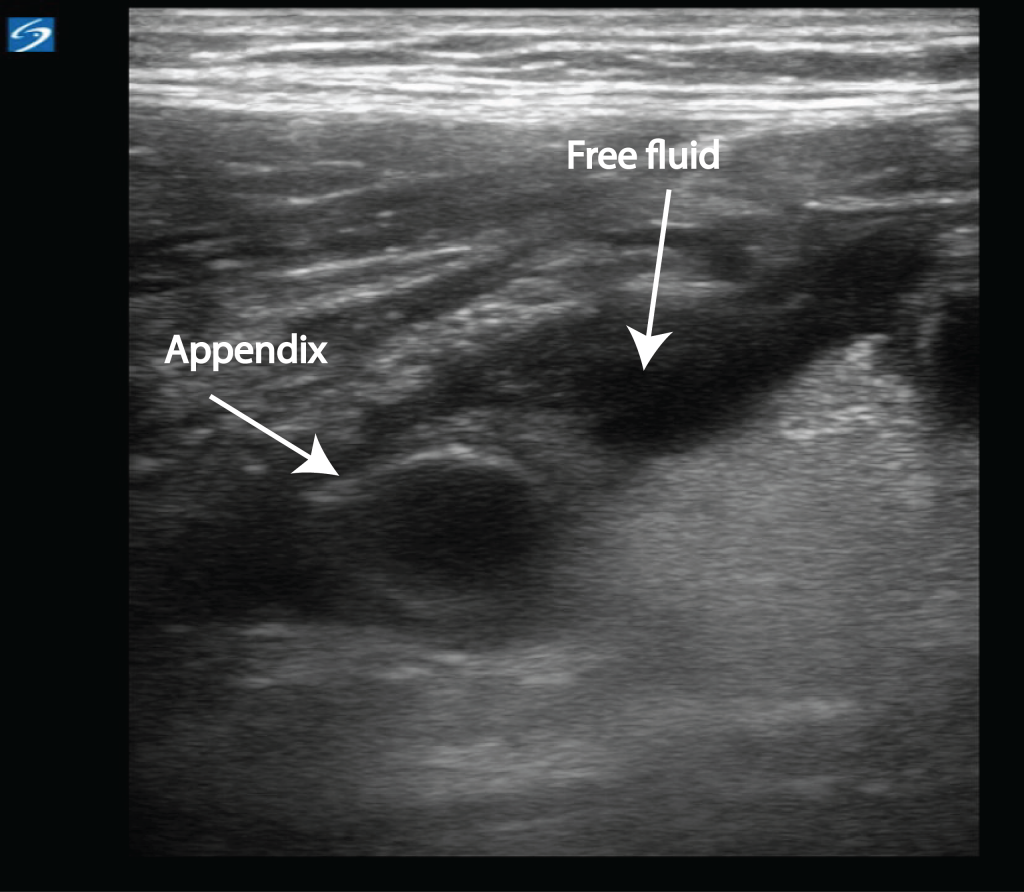

From www.criticalcare-sonography.com

Appendicitis Critical Care Sonography Do You Always Throw Up With Appendicitis  Symptoms of appendicitis usually show up within the first 24 hours and progress. Appendicitis is a medical emergency, whether it's uncomplicated or complicated. With appendicitis, if you have a puking spell, it. Nausea and vomiting are associated with appendicitis, but diarrhea is more consistent with a gastrointestinal infection. This blockage can cause an. If that happens, there’s no time for. Do You Always Throw Up With Appendicitis.